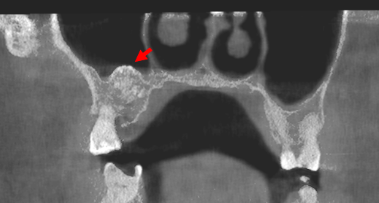

En casos más complejos, el CBCT (tomografía 3D) ofrece imágenes de alta definición, indispensables para valorar la cercanía de las raíces a estructuras nerviosas y reducir riesgos durante la cirugía.

*En la imagen realizada en RD3D observamos los diferentes planos o cortes de un CBCT en el que se señalan las muelas del juicio con su respectivo número de pieza.